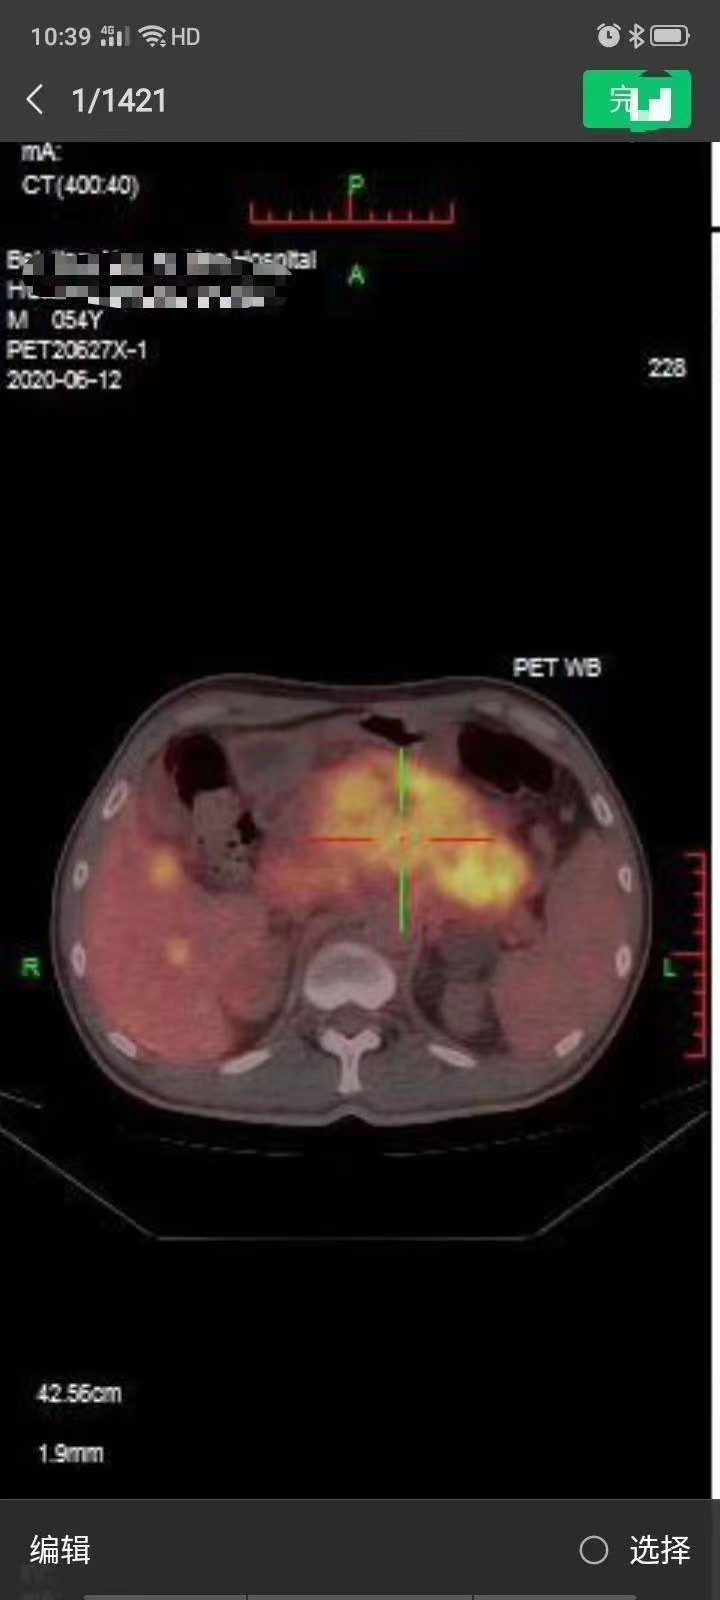

12号术前复查

前两张图是6月份胰腺癌HIFU消融后,总共相差4天,家属和患者对消融效果满意,同道称赞(倪泉兴教授和日本专家)!患者就诊前北大肿瘤医院某专家指示:预计生存期不超过3个月,到目前为止患者已经活了6个月了,查房时,患者有的时候在病房办公,还开玩笑称自己18岁。